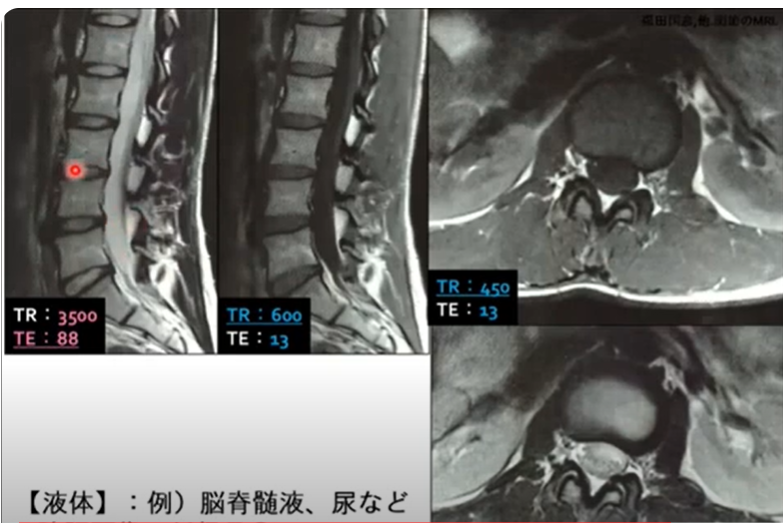

◇MRIを理解しよう!

・まずは“共鳴”と“緩和”について理解しよう

・“T1強調画像”と“T2強調画像”を理解しよう

・“低信号”と“高信号”の意味を理解しよう

・MRIその他の画像1(T2*強調画像、脂肪抑制画像、プロトン密度強調画像)